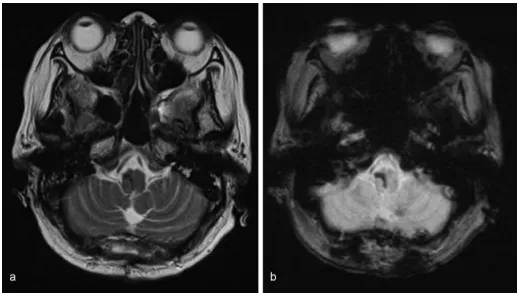

术后患者自主呼吸频率提升至每分钟15次以上。术后第5天停止呼吸机支持,第6天拔除气管插管。术后5周磁共振成像显示无结构异常。康复后患者自主步行出院,未出现进一步并发症。

术后5周磁共振成像未见结构异常。